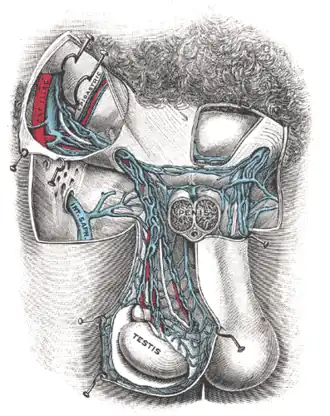

Anatomia

O termo varicocele refere-se especificamente à dilatação e tortuosidade do plexo pampiniforme, que é uma rede de veias que drena o testículo. Este plexo percorre a porção posterior do testículo junto com o epidídimo e o ducto deferente, e então dentro do funículo espermático. Essa rede de veias termina na veia gonadal, ou veia testicular. A veia gonadal direita drena na veia cava inferior, enquanto a veia gonadal esquerda drena na veia renal esquerda, que drena então para a veia cava inferior.

Os pequenos vasos do plexo pampiniforme geralmente variam de 0,5-1,5 mm em diâmetro. A dilatação destes vasos em mais de 2 mm é chamada de varicocele ou varicocelo.